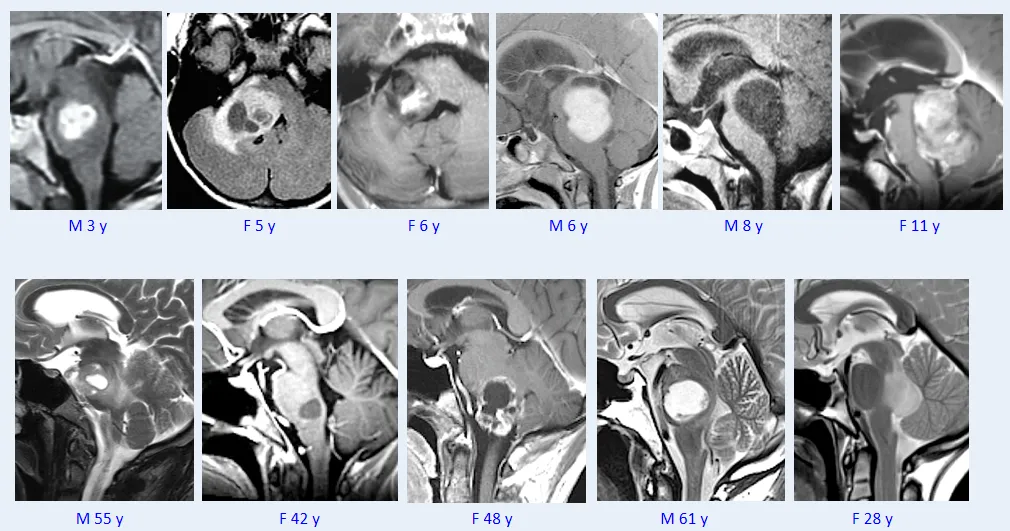

一项研究发现,安全范围内的最大范围手术切除是儿童脑干低级别胶质瘤的首选初始治疗手段。研究《Brainstem Low-Grade Gliomas in Children-Excellent Outcomes With Multimodality Therapy》中10年无进展生存率为71%,总生存率达100%。研究证实,儿童脑干低级别胶质瘤的总体生存率优异。

另一项4040名诊断为低级别胶质瘤儿童患者的长期跟踪结果:监测、流行病学和最终结果数据的分析发现——低级别胶质瘤儿童患者拥有极好的生存率,20年总生存率为87%±0.8%。多因素分析提示,接受放疗是总生存率显著的不利因素。因此,儿童胶质瘤治疗策略应以控制疾病为核心,同时最大限度减少治疗相关的远期毒性。

而,面对脑干胶质瘤,巴教授早已成功手术。

在第四届世界神外顾问团云端峰会时,巴教授就进行了主题为《Surgical treatment of brainstem glioma脑干胶质瘤的外科治疗》的精彩演讲。巴教授精选其206例脑干胶质瘤案例进行了详细的分享,其中大多数都是低级别的毛细胞型星形细胞瘤——脑干不是”无人之地“,对于低级别患者,尤其是毛细胞星形细胞瘤患者,我们甚至可以治愈他们,治愈意味着至少25年无肿瘤进展,而我已经治愈了其中的一些患者。点击阅读:1974-2024携手脑干50年的“love story”「INC云端峰会」巴教授精彩分享